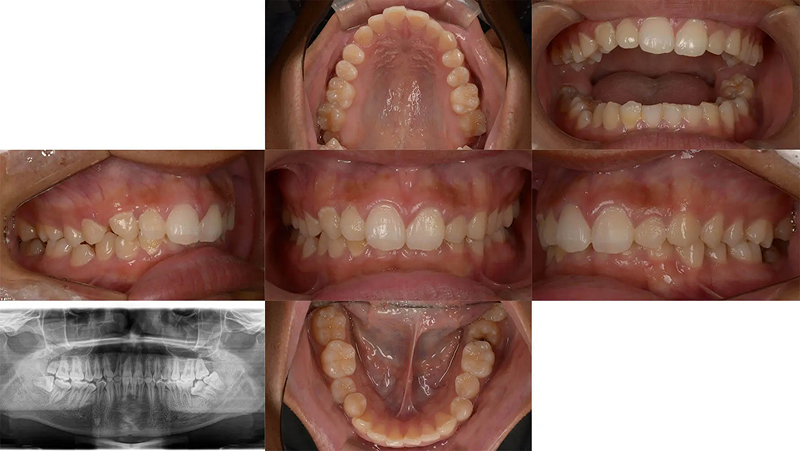

Case01右側奥歯が噛んでいない状態を親知らずを利用し改善した症例

右下第2大臼歯が親知らずの影響で予後不良の状態でした。第2大臼歯を抜歯して、矯正治療で親知らずを利用できないか相談にいらっしゃいました。右側奥歯は交差咬合でしっかり噛めていない状態でした。診査の結果、矯正用アンカーを用いた矯正治療で改善すると診断しました。親知らずは予定通り、第2大臼歯の位置に移動でき、抜歯の跡を隠すことができました。

初診 2016.5.13

矯正開始 2017.6.21

ファイナル 2018.9.4

| 主訴 | 右側奥歯が噛んでいない、親知らずを利用できないか |

|---|---|

| 診断 | 両側アングル1級の叢生 |

| 矯正方法 | 矯正用アンカーを用いたマルチブラケット |

| 矯正期間 | 15か月・17回 |

| 費用 | 730,000円(税別) |

| 調整料 | 月1回 5,000円(税別) |